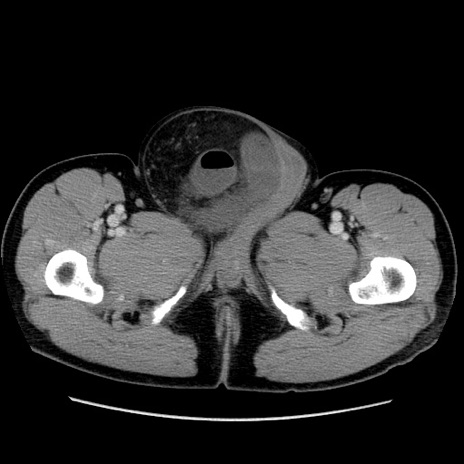

症例34(横断像)

【症例】60歳代 男性

【主訴】右鼠径部膨隆

【現病歴】1年程前より右鼠径部膨隆あり。自己にて還納可能だったため放置していた。3時間前より右鼠径部の脱出を認め、還納困難となり受診。

【既往歴】高血圧

【身体所見】右鼠径部に小児頭大の膨隆あり。弾性硬であり、用手還納は困難。左鼠径部にも膨隆を認める。脱出はなし。